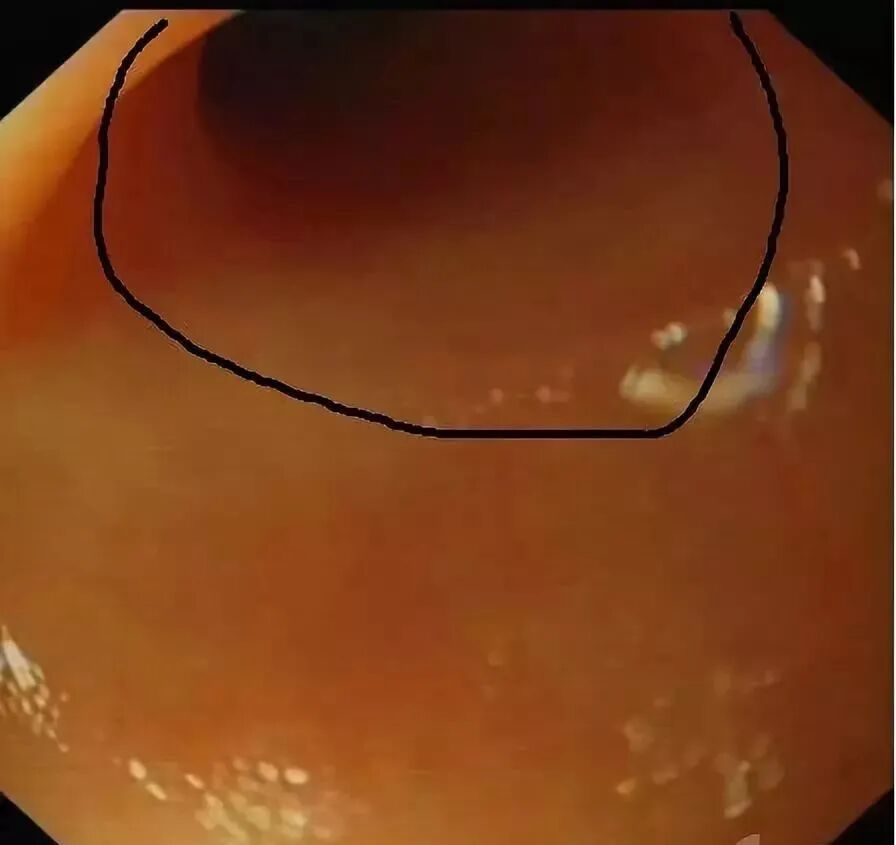

(下图可见白色脓液)

正常的阑尾开口部都被Gerlach’s瓣覆盖(如图,双箭头示Gerlach’s瓣);

通过内镜前端的透明帽的帮助下,推开Gerlach’s瓣(黄箭头),并进行阑尾腔插管。